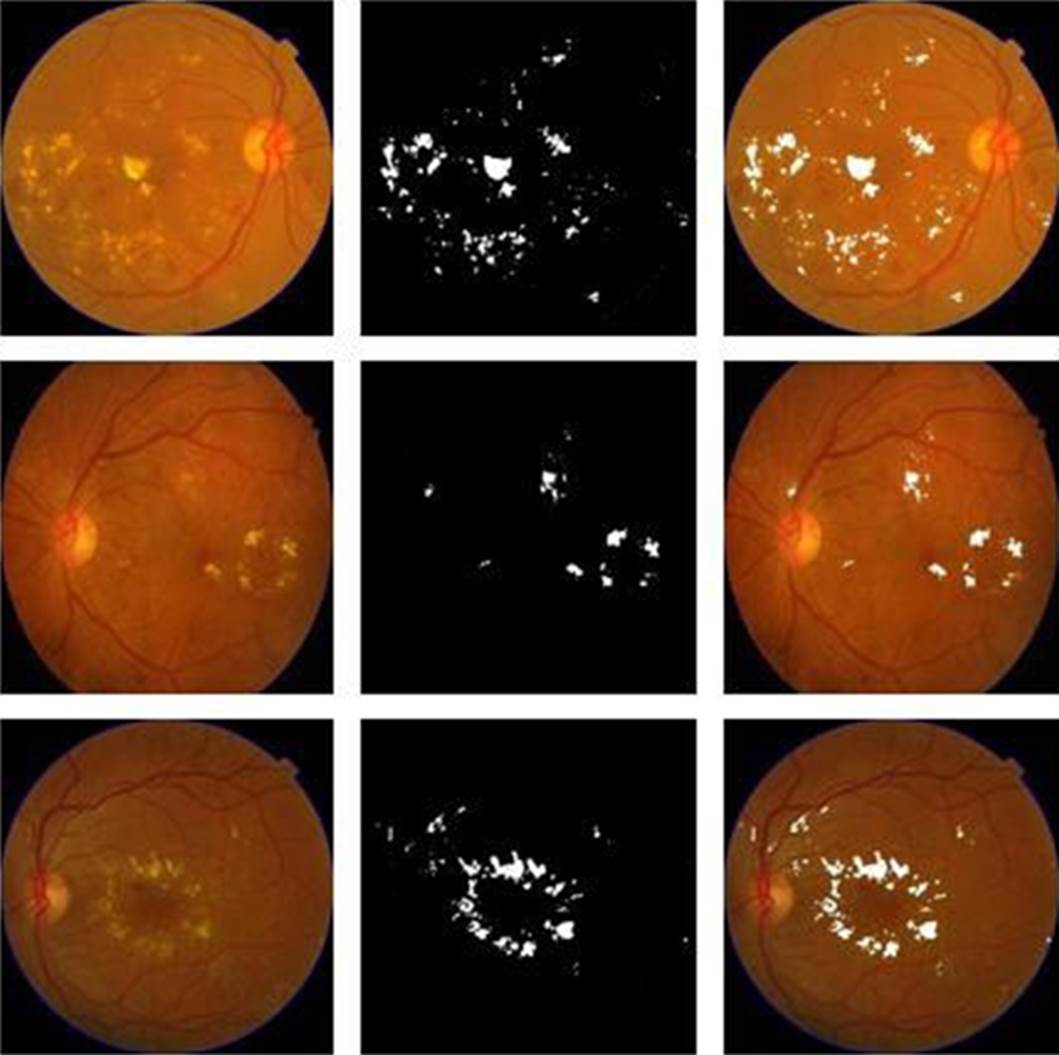

Hard and soft exudates were uniformly detected, looking for the particularity of being shiny objects and thus facilitating their detection. In Figure 7 are shown examples of original retinographies, detection of exudates in binary image and the superposition of the images as a sample of the results obtained.